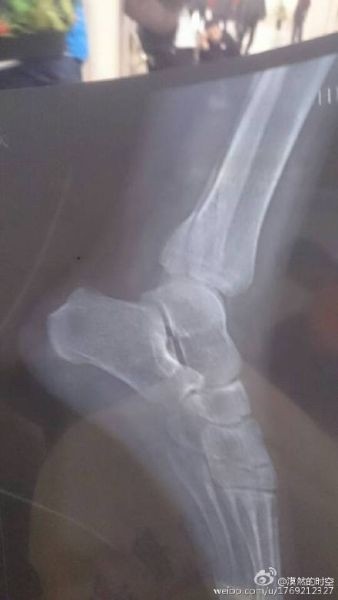

乐极生悲!玩家获激活码回家刷暗黑3致骨折

获得期待已久的《暗黑3》国服激活码本应该是一件十分开心的事情,可微博玩家“漠然的时空”竟在飞奔回家刷章节的路上悲剧的骨折躺到了医院……手机版的炉石传说官博还特地的送上了问候,刚抱怨完“玻璃渣果然人生大坑”的病号玩家便又愉快的搓起炉石了!简直是伤疤未好就忘了疼!